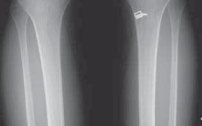

1. Anterior placement of the femoral tunnel is the primary cause of recurrent laxity for ACL reconstructions, so in many cases there is enough room to place a second femoral tunnel in the appropriate position without interference or compromise from the previous tunnel. If this is the case, the previous interference screw can be left in place or removed (

TECH FIG 1C,D

).

1. We have found that transtibially placed femoral tunnels often can be revised by drilling the revision tunnel through the anteromedial portal. In this way, the tunnels diverge, with only the intra-articular outlets overlapping (

TECH FIG 1E

TECH FIG 1 • A. Significant overgrowth of the notch noted at the time of revision anterior cruciate ligament (ACL) reconstruction. B. A thin layer of periosteum is easily visualized at the posterior wall of the notch. C. Note the anterior placement of the femoral tunnel interference screw used during the primary ACL reconstruction. The femoral tunnel for the revision can be placed at the appropriate location without removing the interference screw used in the primary procedure. D. The new femoral tunnel and interference screw are placed in the appropriate location without compromise from the screw used in the index procedure. E. View of femoral notch after placement of femoral tunnel and interference screw via anteromedial portal. This allows divergence of the old and new femoral tunnels.